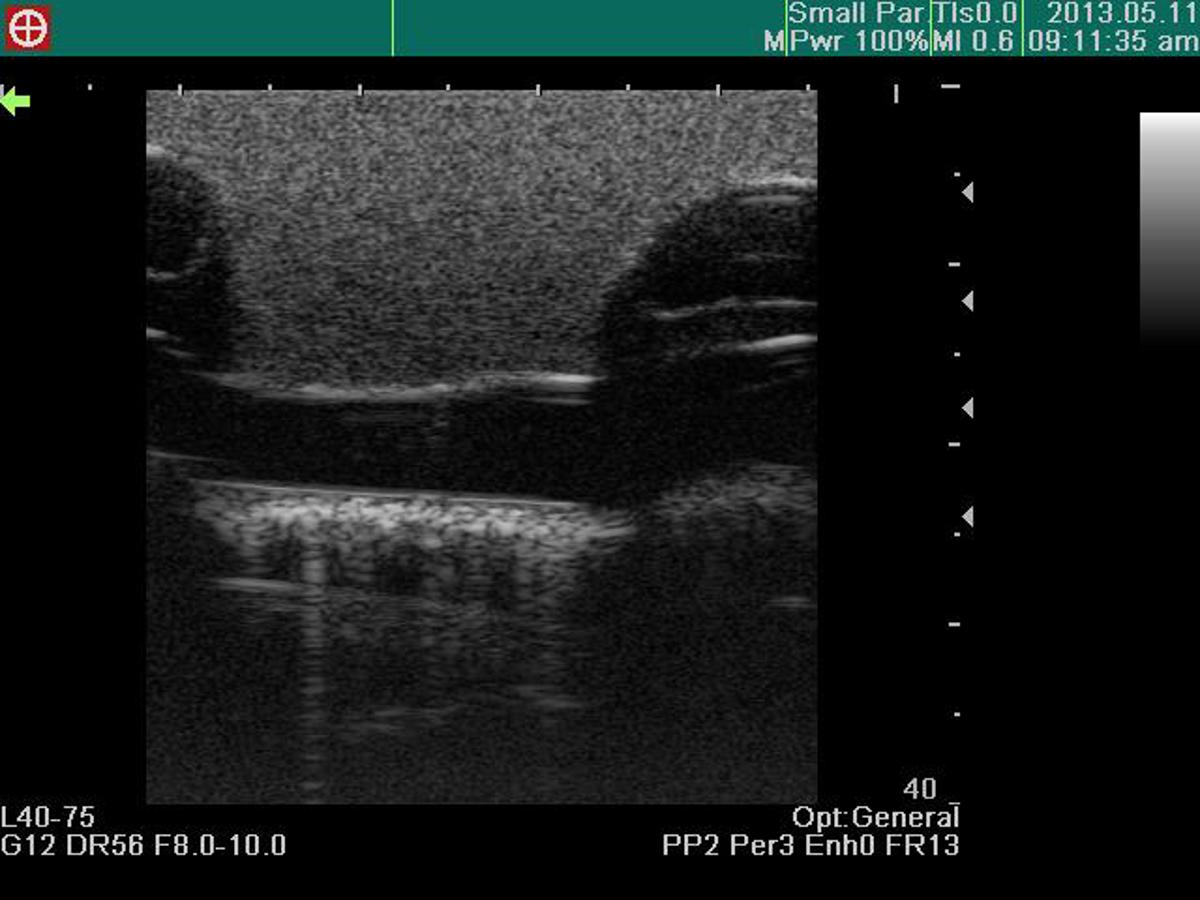

This ultrasound compatible model is a multifaceted trainer that facilitates training in thoracentesis and pericardiocentesis. The combined model allows trainees to use the clear ultrasound image provided to accurately perform both procedures.

Excellent ultrasound image

Anatomically correct puncture sites reproduce realistic needle-top resistance and sensation

Confirmation of ventricles, ribs, pericardium, liver and main artery under ultrasound scanning

Recognition of anatomical landmarks using ultrasound